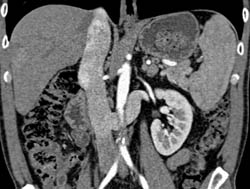

Focal Nodular Hyperplasia (FNH)